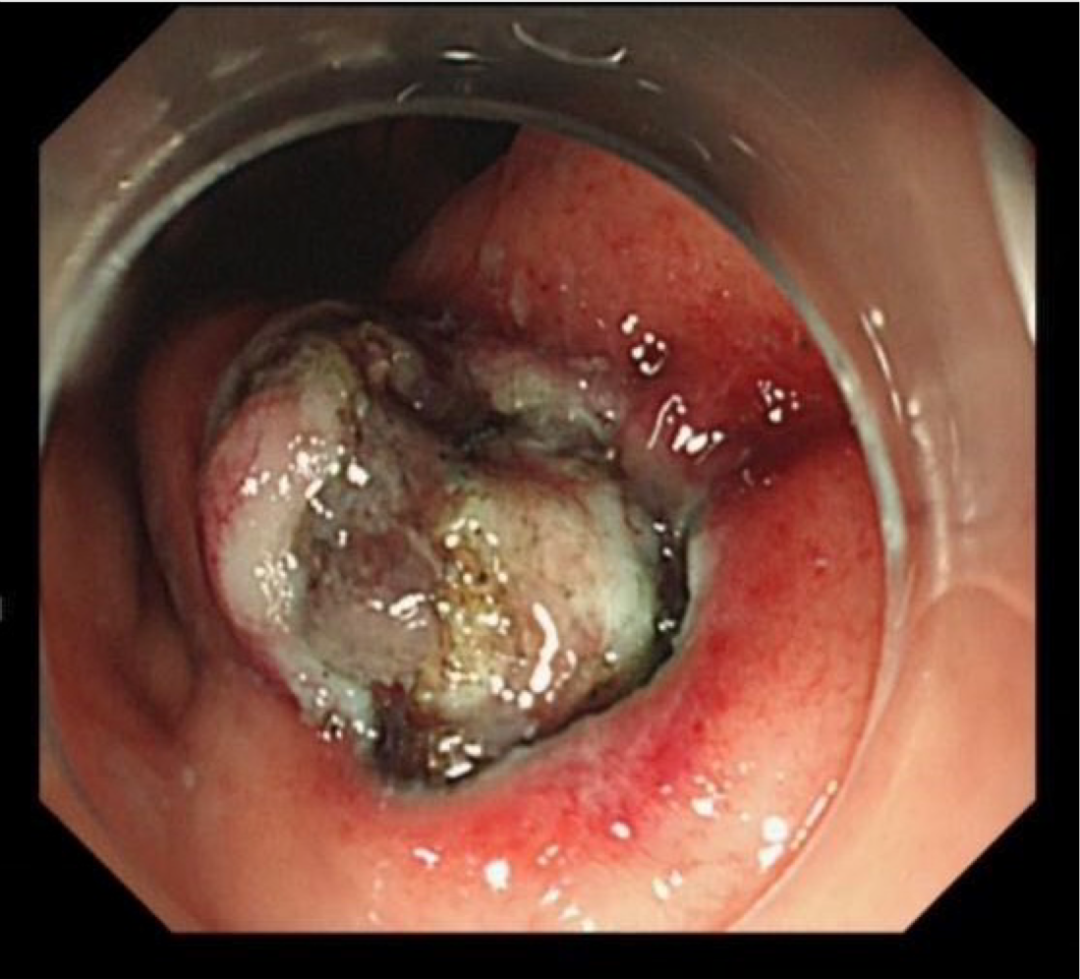

赵某某,男,61岁,因“腹部不适伴大便次数增多2月余”入院,完善肠镜检查:直肠见一直径1.2cm 黏膜下隆起。超声内镜:直肠粘膜肌层低回声隆起,考虑神经内分泌肿瘤。

神经内分泌肿瘤有远处转移可能,与患者家属详细沟通、解释病情,完成充分的术前评估及准备后,孙院长实施黏膜下肿瘤挖除术,成功将病灶切除;术后病理诊断“神经内分泌肿瘤”,患者康复出院。